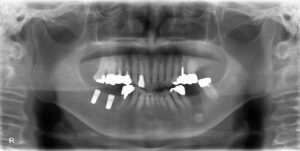

本日は、インプラントの手術を行いました!

以下のレントゲンの画面向かって左側の2本です(^^)/

手術時間40分、術中痛みもなく無事に終了しております。